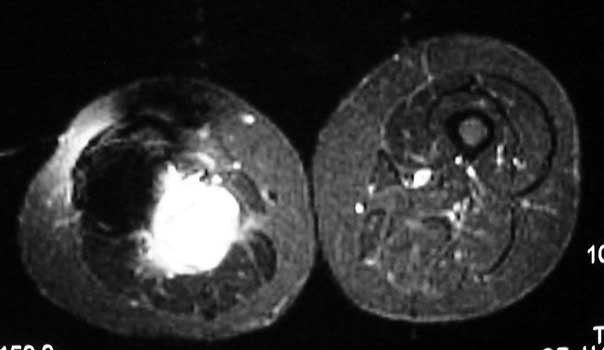

Mass in patient with modular endoprosthesis placed after resection of femur for osteosarcoma. Axial (fig A) and coronal reformatted images (fig B) clearly demonstrate mass adjacent to modular endoprosthesis. 14 gauge core needle biopsy performed under CT guidance (fig C) demonstrated recurrent osteosarcoma

Recurrent osteosarcoma in patient status post resection of femur and placement of modular endoprosthesis. Axial T1 and STIR sequences clearly demonstrate mass adjacent to endoprosthesis.